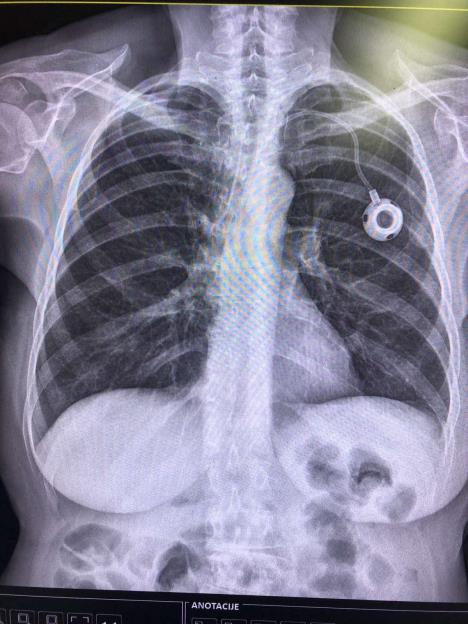

port-na-rendgenskom-snimku-pacijenta.jpg

Foto: Privatna Arhiva

Vaskularni hirurg prof. dr Ivan Marjanović, načelnik Grupe kabineta za hirurške bolesti na Klinici za vaskularnu hirurgiju VMA, objašnjava za Kurir da se port a kat (port a cath), tj. trajni centralni venski kateter zatvorenog tipa, fiksira na nagrudnom mišiću.

- Mora da ga ugradi vaskularni hirurg jer može da se povredi vena, arterija, plućna maramica, grudni koš. To je aparatić koji ima titanijumsko jezerce, kako ga zovemo, i silikonsku membranu. Igla preko koje ide terapija ubada se kroz kožu, na kojoj se port napipa. Preko silikonskog katetera povezan je s desnom pretkomorom srca, odakle se terapija distribuira u organizam. Niko u svetu neće da leči onkološke pacijente bez porta. I ne zbog očuvanja vena nego zato što je port jedini način da budete sigurni da je 100 odsto količine leka koji ste dali otišlo u cirkulaciju. Klasičnim bodenjem u venu iskoristivost leka je 60-70 odsto - ističe prof. Marjanović.

Port, dodaje, može da služi neograničeno i ne nosi nikakve rizike ako se koristi u sterilnim uslovima i održava, što znači i jednom godišnje konzervira, kako se ne bi unela infekcija i ne bi trombozirao.